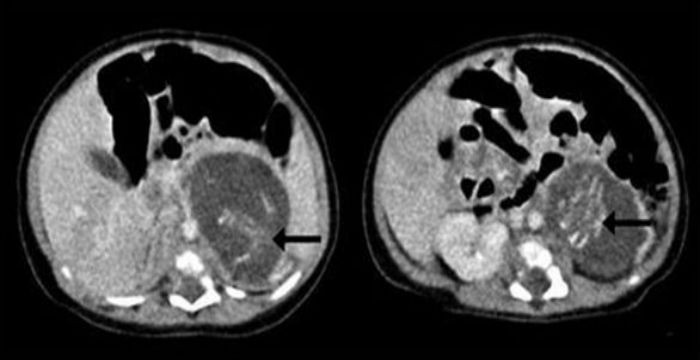

Το κοριτσάκι γεννήθηκε πάνω από 4 κιλά και οι μάζες στην κοιλιά του θεωρήθηκαν ως καρκινικοί όγκοι. Ωστόσο, αξονικές τομογραφίες και άλλες εξειδικευμένες εξετάσεις έδειξαν ότι οι δύο μάζες είχαν σπονδυλική στήλη, ομφάλιο λώρο, άκρα και άλλα χαρακτηριστικά εμβρύου 8 – 10 εβδομάδων.